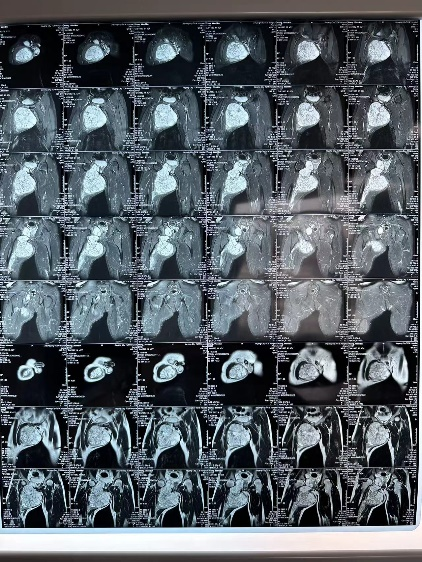

骨科团队

(骨科)